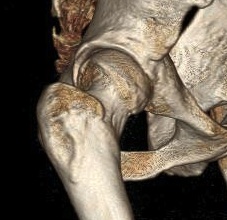

CT

Cam impingement

Pincer